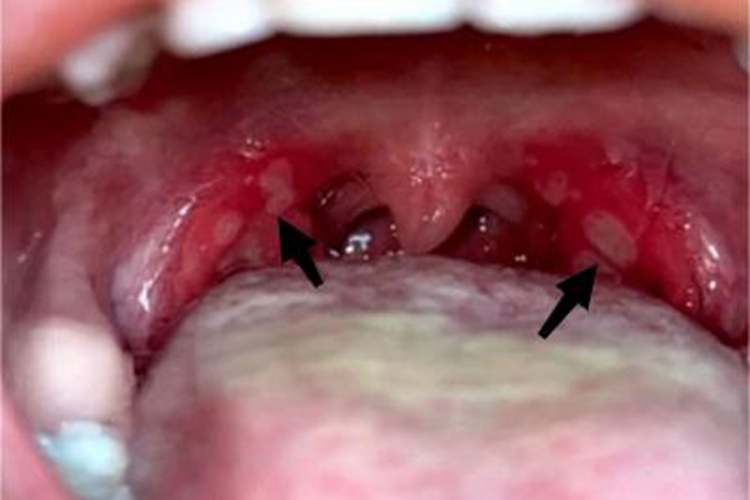

疱疹性咽峡炎可出现溃疡表现,是局部小疱疹破溃形成,患者可自觉有剧烈疼痛感。

疱疹性咽峡炎的典型症状为患处出现小疱疹,随着疾病的发展,疱疹破裂形成边界清晰的溃疡,溃疡边缘有明显的红晕,患者自觉有剧烈疼痛感。